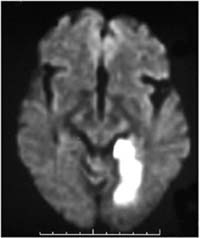

IRM accident ischémique cérébral postérieur droit

L'IRM montre une lésion du territoire profond de la région postérieure droite de l'encéphale.

Cette lésion est ici consécutive à une ischémie, c'est à dire une diminution ou une interruption de la circulation artérielle dans ce territoire. L'ischémie entraîne un défaut d'apport en oxygène aux neurones, d'où la nécrose (mort) des tissus concernés.